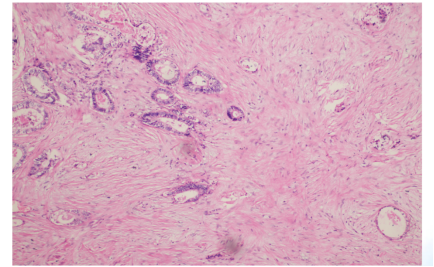

2024年7月31日肠镜检查:距肛门15 cm见环周型粘膜肿块,活检示乙状结肠腺癌。

2024年8月8日,患者因有肠道梗阻症状进行了肠镜支架植入术(图4)。病检显示结肠中分化腺癌,MLH1(+),MSH2(+),MSH6(+),PMS2(+),Syn(-),CD56(-), her2(0)。

术后病理显示(图13),乙状结肠中-低分化腺癌,侵及肠壁全层及肠外脂肪层,见大片坏死伴广泛纤维增生及急慢性炎症细胞浸润,化疗后TRG 2级(AJCC评分标准),未见明确神经及脉管侵犯,肿瘤出芽分级:Bd1级。近、远及放射状切缘未见癌累及。肠周淋巴结未见癌转移(0/21),网膜未见癌组织。Ki67 60%(+),MLH1(+),MSH2(+),MSH6( +),PMS2(+),her2(0)。